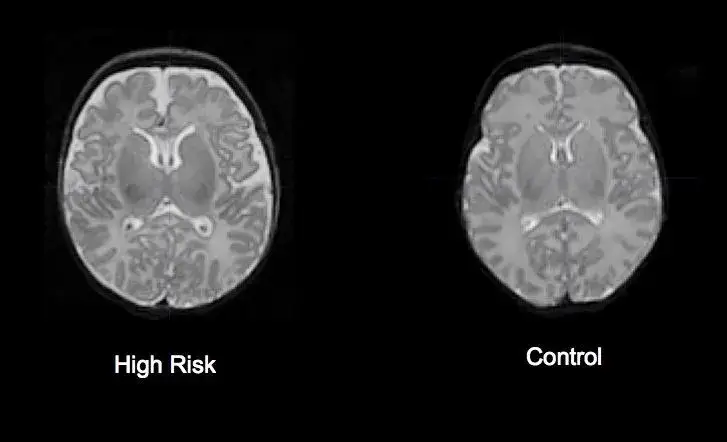

ADHD: Jak obrazowanie mózgu potwierdza neurobiologiczne podłoże zaburzenia?

Mniejsza objętość kluczowych struktur: Które obszary mózgu rozwijają się inaczej?

Badania strukturalne MRI u osób z ADHD konsekwentnie wykazują pewne różnice w objętości kluczowych struktur mózgu w porównaniu do osób bez tego zaburzenia. Obserwuje się mniejszą objętość całkowitą mózgu, a także specyficzne zmniejszenie objętości w rejonach takich jak:

Te zmiany korelują z typowymi objawami ADHD, takimi jak problemy z koncentracją, impulsywność i nadruchliwość, potwierdzając neurobiologiczne podłoże tego zaburzenia. Ważne jest, aby pamiętać, że są to różnice statystyczne, a nie absolutne markery diagnostyczne.

Opóźnione dojrzewanie kory przedczołowej a problemy z koncentracją i impulsywnością

Czy obraz MRI u dziecka z ADHD różni się od obrazu osoby dorosłej?

Tak, istnieją pewne różnice rozwojowe w wynikach MRI dla ADHD między dziećmi a dorosłymi, co dodatkowo wzmacnia ideę opóźnionego dojrzewania. U dzieci z ADHD różnice w objętości struktur mózgu są zazwyczaj bardziej wyraźne. Wraz z wiekiem, w procesie dojrzewania, mózg osób z ADHD może częściowo "dogonić" rozwój mózgu rówieśników, co jest zgodne z obserwacją, że u wielu osób objawy ADHD mogą się łagodzić w dorosłości. Jednakże, nawet u dorosłych z ADHD, subtelne różnice w strukturze i funkcjonowaniu mózgu mogą nadal być widoczne. Te obserwacje podkreślają dynamiczny charakter rozwoju mózgu i wpływ ADHD na ten proces na różnych etapach życia.